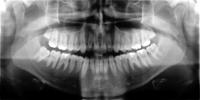

OPG

Das Orthopantomogramm  ist eine Aufnahme beider Kiefer mit dessen Hilfe der Zustand der Zähne, der Verlauf des Zahndurchbruchs und die Lage der Zahnkeime im Kiefer beurteilt wird.